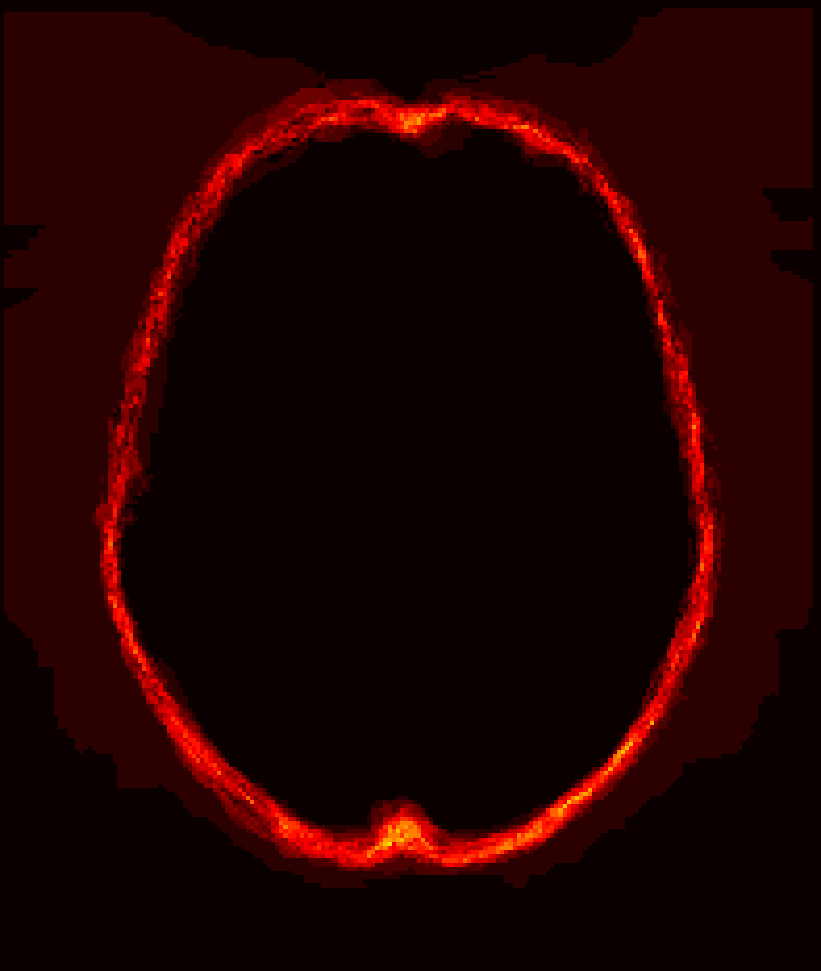

Fig. 1 shows example images from each dataset to illustrate image variability. IBSR and LPBA40 contain images from normal subjects and include large portions of the neck; BRATS has very low out-of-plane resolution; and the TBI dataset contains large pathologies and abnormal skulls.

Refer to caption

Figure 1: Illustration of image appearance variability on a selection of images from each (evaluation) database. From top to bottom: IBSR, LPBA40, BRATS and TBI.